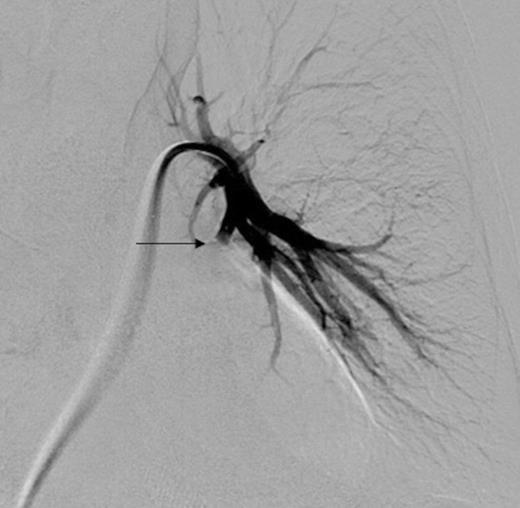

Digital subtraction angiography post deployment of the AVP 4 device in the PA branch feeding the aneurysm (arrow). No residual or collateral filling seen

Using the right femoral vein for access, a 5 FR (French) pigtail catheter was advanced into the main left pulmonary artery. Angiography demonstrated the vascular anatomy in relation to the PAA (Figure 2). The pigtail catheter was then exchanged for a 7 FR Destination access sheath (Terumo, Japan). A 5 FR multipurpose catheter and hydrophilic guidewire combination was used to selectively catheterise the segmental left lower pulmonary arterial branch feeding the aneurysm (Figure 3). This was followed by deployment of a single 7mm Amplatzer® Vascular Plug 4 (AVP 4) in the feeding branch, with preservation of the surrounding pulmonary artery branches (Figure 4). A repeat CTPA was undertaken 2 days later, confirming satisfactory PAA exclusion, with no evidence of residual filling (Figure 5). The patient made an uncomplicated recovery and was discharged home, but unfortunately died 6-months later from metastatic disease.